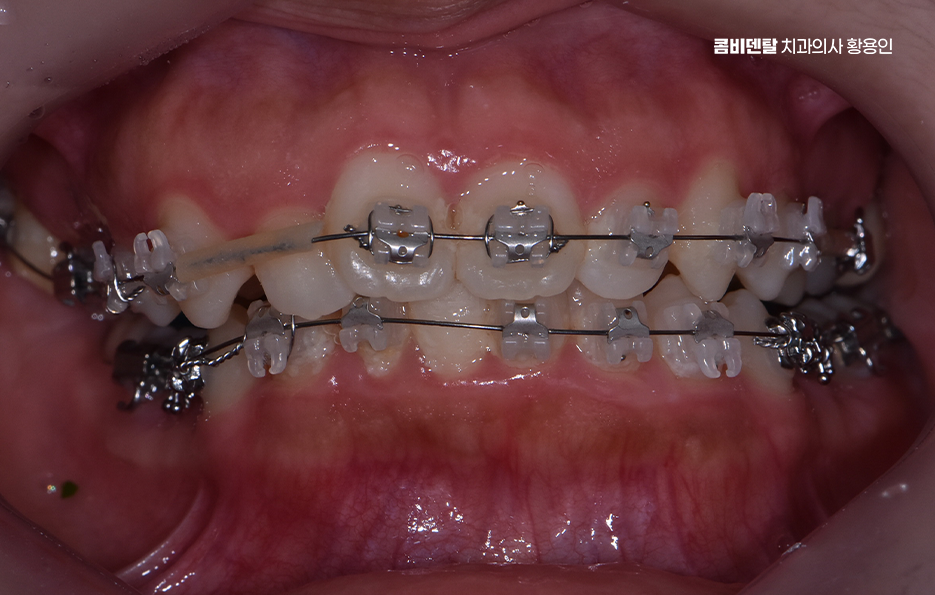

비발치 돌출입 교정 가능한 대표적인 케이스는 치아 배열의 공간이 비교적 충분한 경우로서 치아가 전체적으로 가지런하지는 않지만, 심하게 겹쳐 있지 않고 잇몸뼈 안에 어느 정도 여유 공간이 있는 경우에는 발치 없이도 치아를 뒤쪽으로 이동시키는 것이 가능한 경우가 있었어요.

특히 앞니가 약간 앞으로 기울어져 있으면서 입술 돌출이 심하지 않은 경우에는 비발치 교정으로도 인상 개선 효과를 기대할 수 있어요.

비발치 돌출입 교정에서 주로 사용되는 방법 중 하나는 악궁 확장으로 치아가 나 있는 폭을 넓혀서 공간을 확보한 뒤, 치아를 재배열하는 방식인데 이 방법은 공간을 만들어 발치 없이 교정을 진행할 수 있다는 장점이 있지만, 무리한 확장은 잇몸이나 치아 뿌리에 부담을 줄 수 있기 때문에 한계 범위 안에서만 적용되고 있어요

또 다른 비발치 방법은 어금니를 뒤쪽으로 이동시키는 방식으로 어금니를 뒤로 보내서 앞니가 들어갈 공간을 만드는 개념이며 치간 삭제 라는 방법도 있는데 치아 사이의 공간을 미세하게 조절하여 치아의 건강은 해치지 않으면서 치아의 이동 공간을 확보하는 방식이라 할 수 있었어요